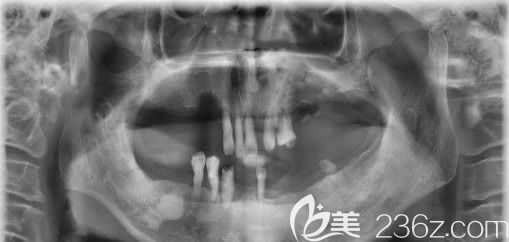

种牙前的CT片,牙齿掉的只剩9颗松动牙,让我吃饭成为了一种折磨:↑↑